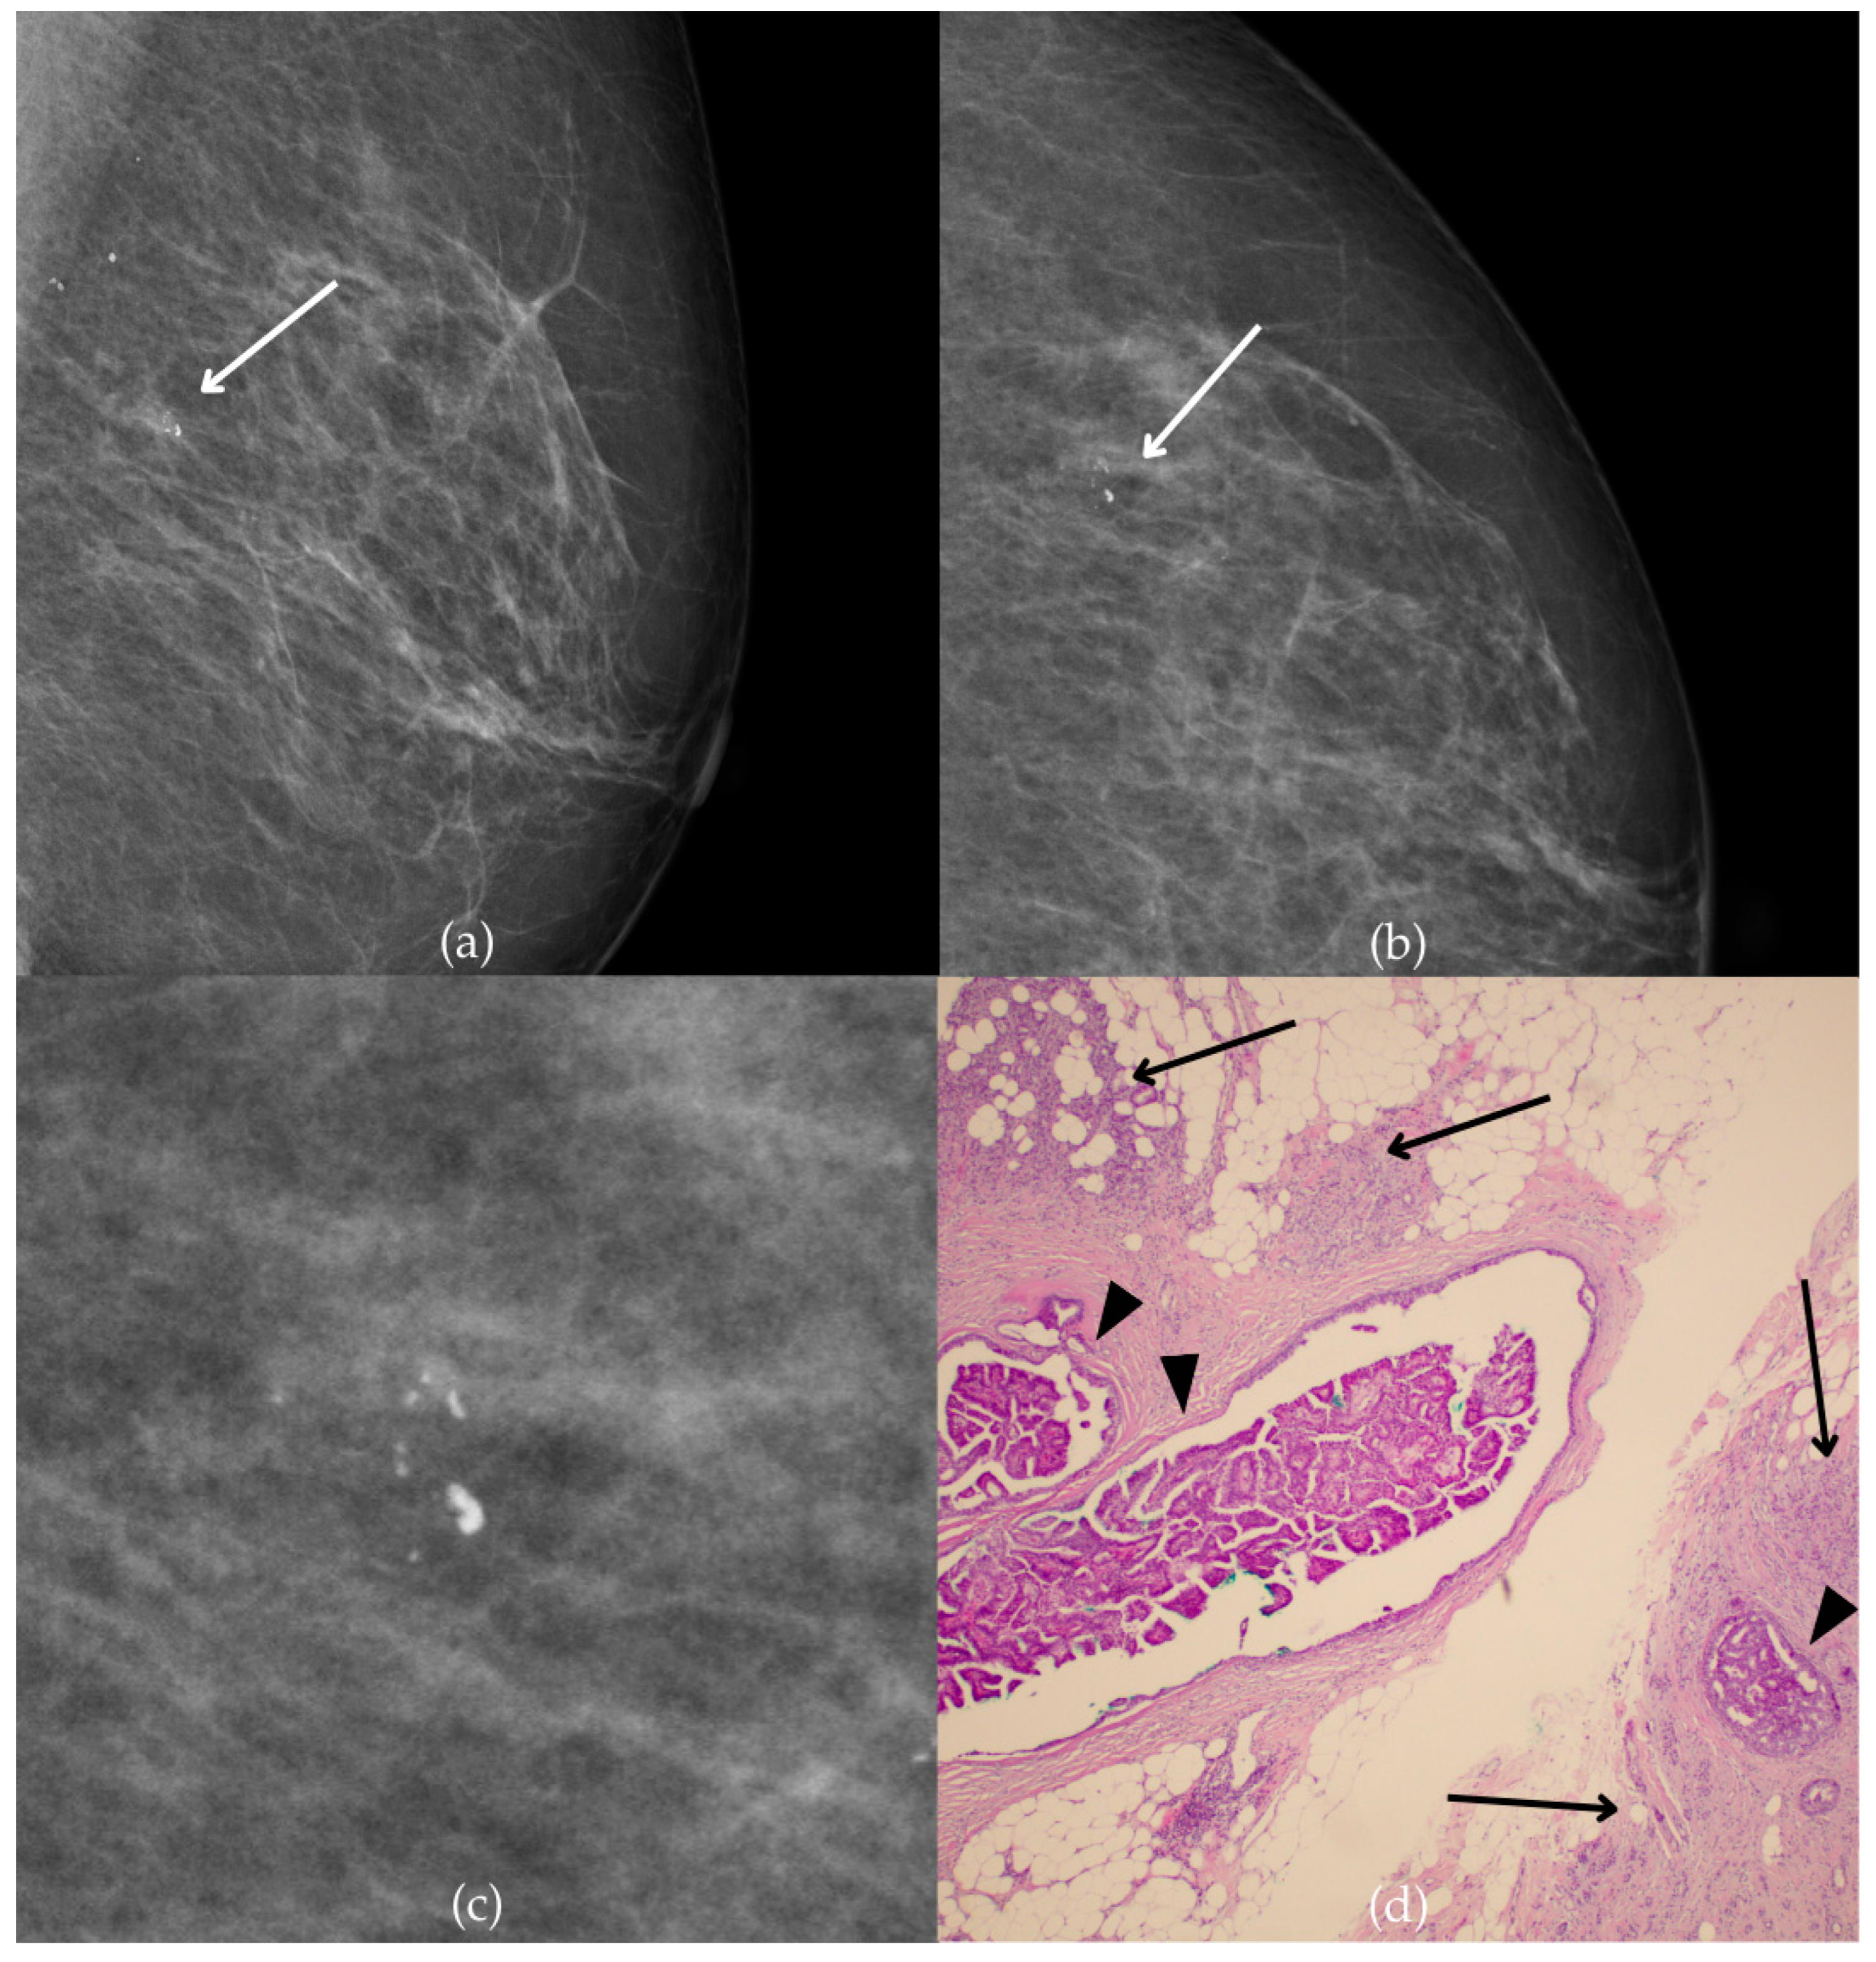

Mammogram and histopathological images (Figure 10) of a 66-year-old patient’s right breast show architectural distortion with associated fine pleomorphic calcifications of segmental distribution in the upper outer quadrant, corresponding to a BI-RADS 3 finding. Tissue analysis obtained through biopsy reported an intraductal papillary lesion without epithelial atypia (category B3). The patient underwent an excisional biopsy (quadrantectomy), and postoperative pathology confirmed the absence of carcinoma. One year after the initial diagnosis, the most recent US follow-up was classified as BI-RADS 2, confirming benign findings.

Figure 10.

Intraductal papillary lesion without epithelial atypia. (a) Mediolateral oblique (MLO) view; (b) craniocaudal (CC) view of the right breast showing architectural distortion with associated fine pleomorphic calcifications of segmental distribution (marked with arrows) in the upper outer quadrant. (c) Magnified mammographic image of fine pleomorphic calcifications of segmental distribution. (d) The histopathological image of the biopsy sample shows an intraductal papillary lesion without epithelial atypia (HE staining; 40× magnification).